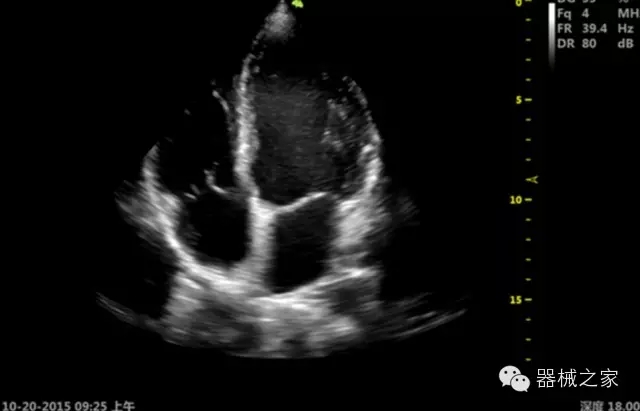

臨床圖片賞析

優(yōu)異的成像技術

·亞陣元技術:獨有的亞陣元技術,對獨立晶片做二次切割,減少旁瓣偽像,增加臨床診斷的準確性;

·μ-Scan微米成像技術:開立獨有的μ-Scan技術,還原出真實細膩、層次對比優(yōu)異的二維圖像;

·倒相諧波成像技術:倒相諧波技術在去除基波信號的基礎上獲取兩倍二次諧波信號,提高組織圖像的對比分辨力;

·智能微血流成像技術:智能微血流捕捉技術可以提取出隱藏在背景噪聲中的弱血流信號,大大提高低速血流的敏感性;

超聲科常規(guī)領域應用

·移植S40高端臺式彩超高端平臺技術,滿足超聲科腹部、淺表、婦產(chǎn)科、心血管、肌骨等應用,提供超聲科完美解決方案;

·心功能綜合指數(shù)(TEI指數(shù)):用于左、右心室整體心臟收縮舒張功能評估的測量方法;

·全方位可調(diào)M型:有利于更好的觀察心腔大小及室壁階段性運動的異常情況;

·組織多普勒成像(TDI):TDI可定量評價心肌運動,判斷是否有局部病變,還可評價早期的舒張功能;